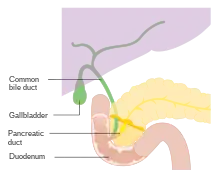

The biliary tract refers to the path by which bile is secreted by the liver then transported to the duodenum, the first part of the small intestine. A structure common to most members of the mammal family, the biliary tract is often referred to as a tree because it begins with many small branches that end in the common bile duct, sometimes referred to as the trunk of the biliary tree. The duct, the branches of the hepatic artery, and the portal vein form the central axis of the portal triad.[7] Bile flows in the direction opposite to that of the blood present in the other two channels.[8]

- Bile canaliculi >> Canals of Hering >> intrahepatic bile ductule (in portal tracts / triads) >> interlobular bile ducts >> left and right hepatic ducts[4]

- These merge to form the common hepatic duct[4]

- The common hepatic duct exits the liver and joins with the cystic duct from gall bladder[4]

- Together these form the common bile duct which joins the pancreatic duct[4]

- These pass through the ampulla of Vater and enter the duodenum[4]

Bile is secreted by the liver into small ducts that join to form the common hepatic duct.[2] Between meals, secreted bile is stored in the gall bladder, where 80–90% of the water and electrolytes can be absorbed, leaving the bile acids and cholesterol.[5] During a meal, the smooth muscles in the gallbladder wall contract, causing bile to be secreted into the duodenum to rid the body of waste stored in the bile as well as aid in the absorption of dietary fats and oils by solubilizing them using bile acids.[5]

Occasionally gallstones may become lodged in the common bile duct and obstruct the flow of bile from the gallbladder to the small intestine– this condition is known as choledocholithiasis[11] and is another indication for cholecystectomy.[12] The common bile duct, commonly abbreviated CBD, is formed by the union of the cystic duct and common hepatic duct, and it later joins the pancreatic duct to terminate in the Ampulla of Vater at the small intestine. The function of the common bile duct is to allow bile to travel from the gallbladder to the small intestine, mixing with pancreatic digestive enzymes along the way.[4] One possible complication of choledocholithiasis is an infection of the bile ducts between the liver and the gallstone lodged in the common bile duct. This condition is known as acute cholangitis and is commonly associated with a triad of clinical symptoms known as Charcot's Triad, which includes fever, right upper quadrant abdominal pain, and jaundice.[11] This constellation of symptoms has a 96% specificity for cholangitis,[11] and can be expanded upon with the addition of hypotension and altered mental status to form Reynold's Pentad.[11]